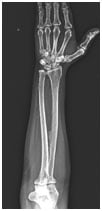

The x ray of the forearm showed interosseous membrane calcification, which was diagnostic of fluorosis. Skeletal fluorosis is endemic in certain regions of India, especially in patients from rural areas where untreated underground water is major source of water for drinking and daily use. This case highlights the importance of considering patients epidemiological scenarios with imaging finings before coming to final diagnosis.